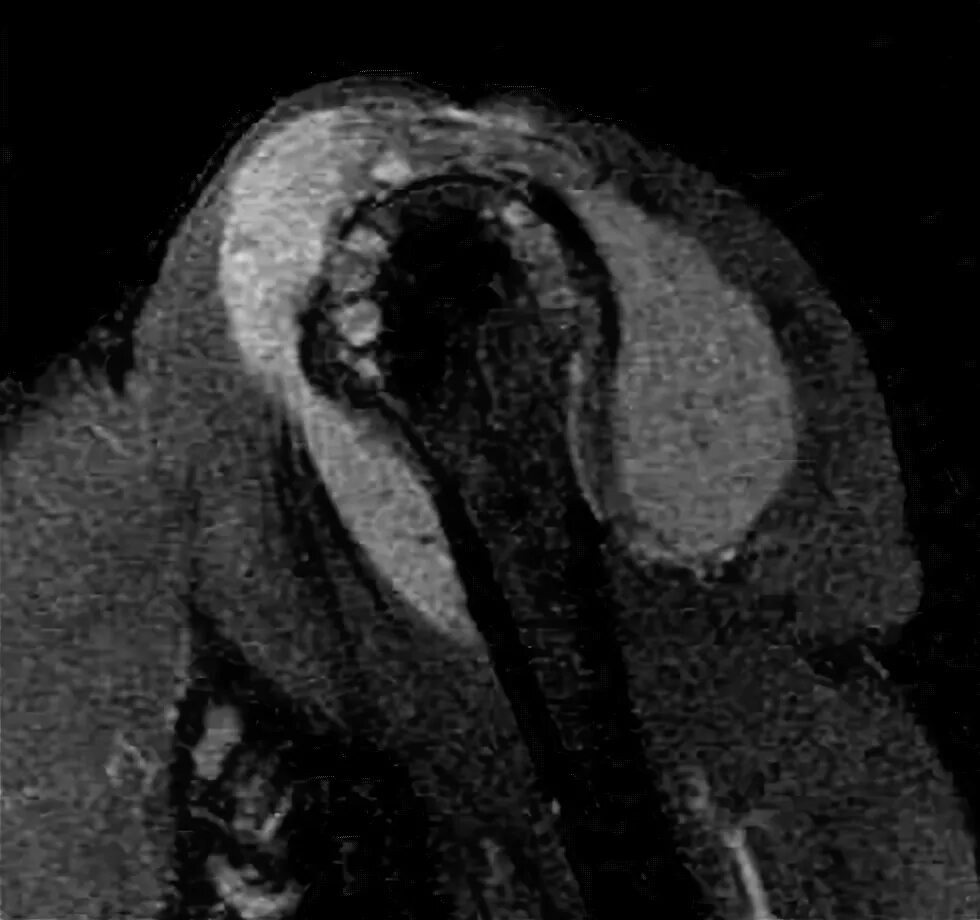

Пигментный виллонодулярный синовит